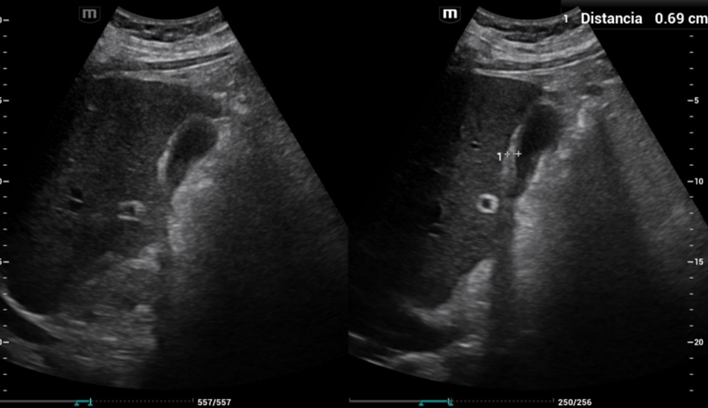

1.ª ecografía: hepatomegalia, distensión de venas suprahepáticas y vesícula biliar de paredes engrosadas.

2.ª ecocardioscopia POCUS: derrame pleural, septo ventricular engrosado, hipoquinesia severa global, patrón de llenado ventricular restrictivo y derrame pericárdico.